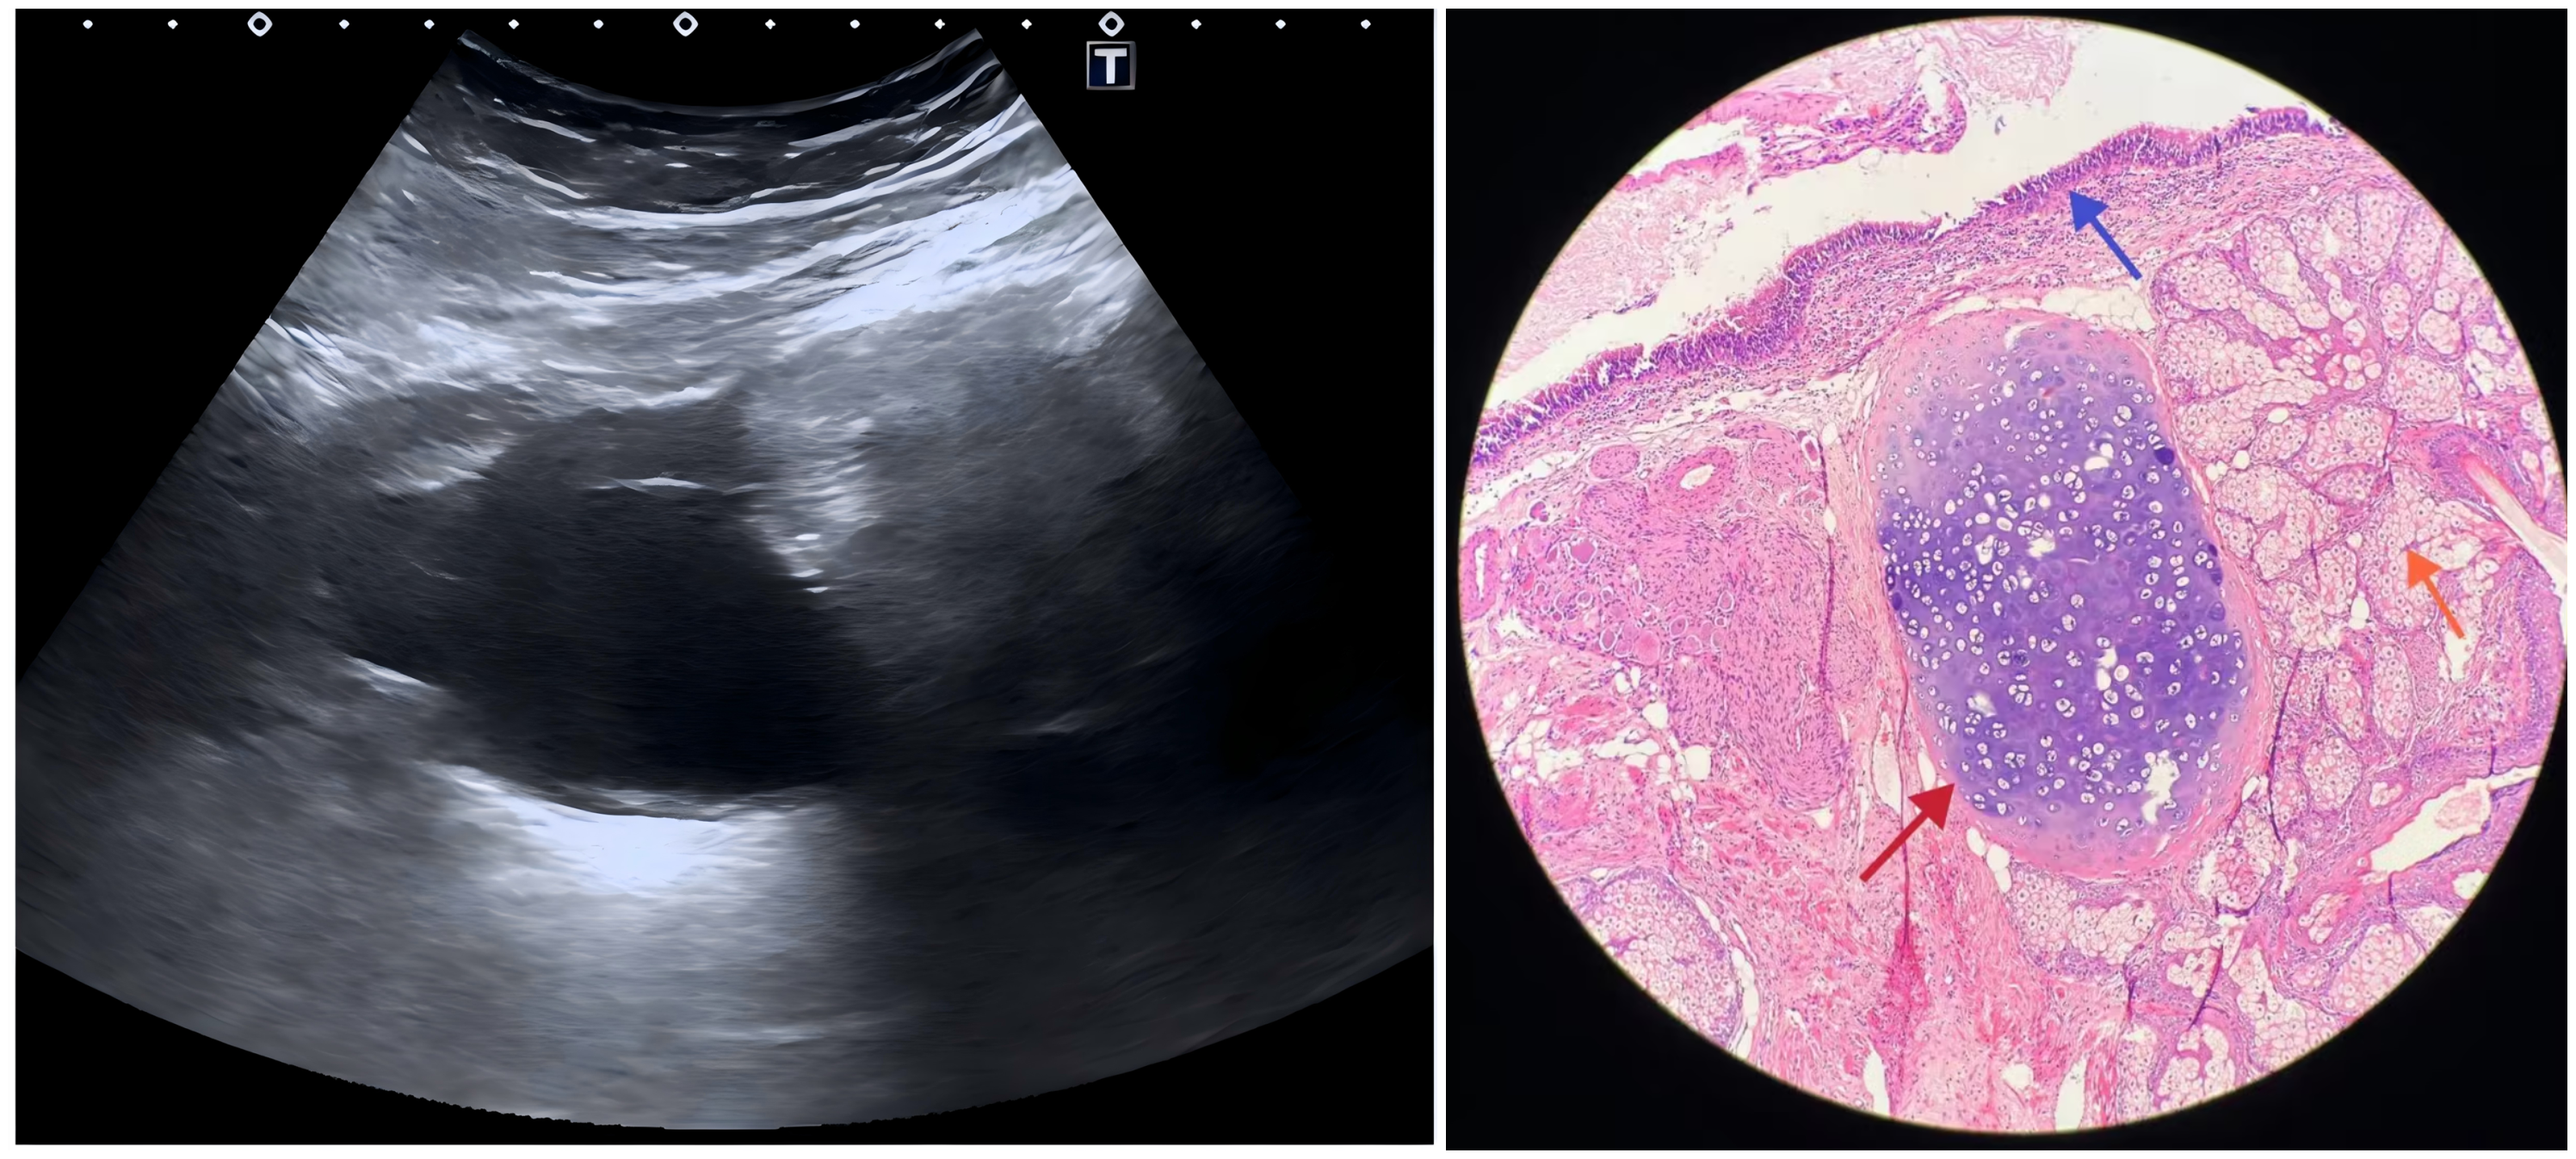

触感:B超下像一枚充满油脂的“荷包蛋”,里面漂着高回声的小亮点——那就是毛发或牙齿。

成分:外胚层(皮肤、神经)、中胚层(骨、软骨)、内胚层(呼吸道或胃肠道上皮)都可能出现。

“超声先开口,CT/MRI加证据,病理说了算”,即可完成卵巢畸胎瘤的精准确诊。